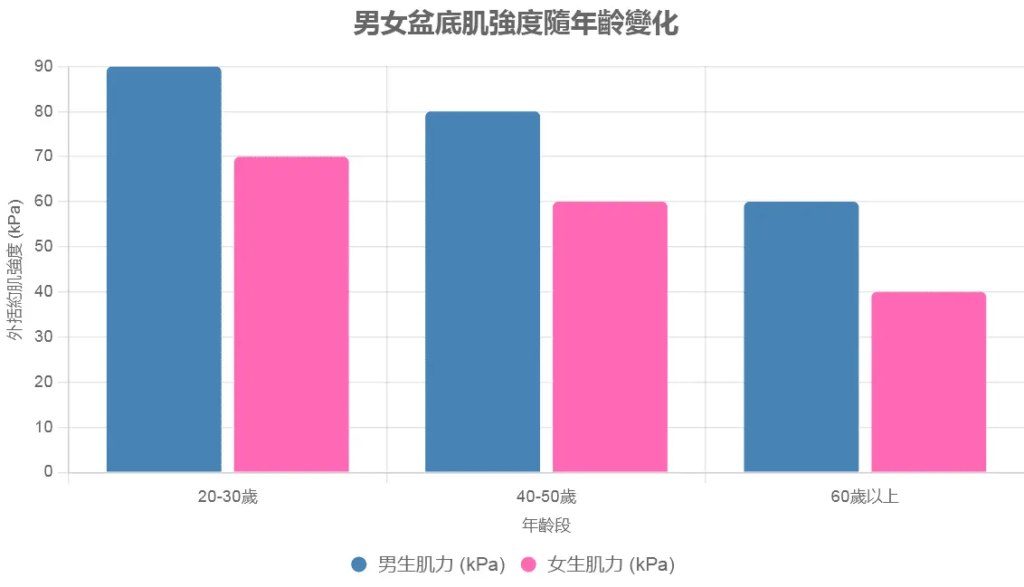

圖表展示:男女盆底肌強度比較(基於模擬數據,單位:肌收縮力,kPa)

使用表格呈現假設數據(來自研究平均值):

| 年齡群組 | 男生平均外括約肌強度 (kPa) | 女生平均外括約肌強度 (kPa) | 差異原因 |

|---|---|---|---|

| 20-30歲 | 80-100 | 60-80 | 雄激素高峰 vs 雌激素波動 |

| 40-50歲 | 70-90 | 50-70 | 前列腺輕微增大 vs 懷孕影響 |

| 60歲以上 | 50-70 | 30-50 | 年齡衰退 vs 更年期低雌激素 |

此圖表顯示,隨著年齡增長,女生肌力衰退更快,導致控制差異放大。

描述:

此柱狀圖比較不同年齡段(20-30歲、40-50歲、60歲以上)男女的外括約肌與盆底肌強度(單位:kPa)。每個年齡段有兩柱:

- 男生柱(深藍):顯示20-30歲肌力80-100 kPa,40-50歲70-90 kPa,60歲以上50-70 kPa。

- 女生柱(粉紅):顯示20-30歲60-80 kPa,40-50歲50-70 kPa,60歲以上30-50 kPa。

柱高差異反映雄激素(睪固酮)與雌激素的影響:男生肌力隨年齡緩慢下降,女生因更年期雌激素驟降,肌力衰退更快。

原因分析:

柱狀圖顯示,男生肌力始終高於女生,尤其在60歲以上,差距達20-30 kPa。這與雄激素穩定肌力、雌激素波動導致肌鬆弛有關。女生更年期後(約50歲起),雌激素下降30-50%,失禁風險增2倍。